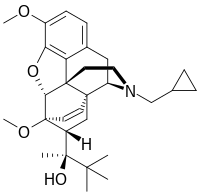

Oripavine derivatives

Thienorphine

- 7-PET

- Acetorphine

- Alletorphine (N-allyl-noretorphine)

- BU-48

- Buprenorphine

- Buprenorphine-3-glucuronide

- Cyprenorphine

- Dihydroetorphine

- Etorphine

- Homprenorphine

- 18,19-Dehydrobuprenorphine (HS-599)

- N-cyclopropylmethylnoretorphine

- Nepenthone

- Norbuprenorphine

- Norbuprenorphine-3-glucuronide

- Thevinone

- Thienorphine

Structures

| Oripavine derivatives | ||||

|---|---|---|---|---|

7-PET 7-PET |

Acetorphine Acetorphine |

Alletorphine Alletorphine |

BU-48 BU-48 |

Buprenorphine Buprenorphine |

Cyprenorphine Cyprenorphine |

Dihydroetorphine Dihydroetorphine |

Etorphine Etorphine |

Homprenorphine Homprenorphine |

18,19-Dehydrobuprenorphine 18,19-Dehydrobuprenorphine |

N-cyclopropylmethylnoretorphine N-cyclopropylmethylnoretorphine |

Nepenthone Nepenthone |

Norbuprenorphine Norbuprenorphine |

Thevinone Thevinone |

Thienorphine Thienorphine |